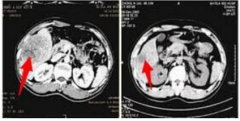

脑膜瘤3cm-4cm严重吗?脑膜瘤不开刀能活多久? 脑膜瘤(Meningiomas)是一种长在脑膜及脑膜间隙的的肿瘤,在颅内常见,80%以上脑膜瘤都是良性的肿瘤。典型的脑膜瘤,在未增强的CT扫描中...